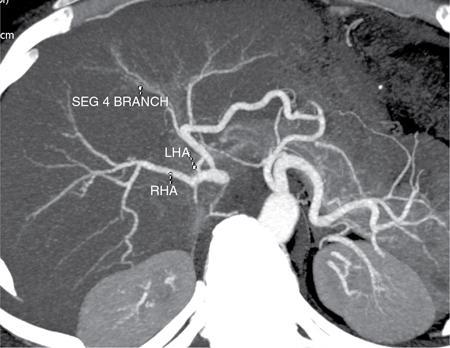

Ritu K. Kashikar, Shrinivas B. Desai Imaging is the mainstay of noninvasive diagnosis of the spectrum of abdominal pathologies or proving absence off thereof. Knowledge of normal anatomy and important normal variants is thus essential for the radiologist in order to avoid misinterpretation or erroneous diagnosis. This chapter highlights the normal anatomy of the hepatobiliary systems including the blood vessel and draining ducts and discusses relevant anatomical variants which may have important clinic implications. The liver is the largest abdominal organ, occupying the right upper abdominal quadrant and is in close approximation with the diaphragm, stomach and the gallbladder. It is largely covered by the costal cartilages. The liver is encapsulated by Glisson’s capsule which is a dense layer of connective tissue. It is covered by peritoneum, except in the regions of gallbladder fossa, fossa for inferior vena cava (IVC), and the bare area. The bare area is the posterocranial aspect of the liver, adjacent to the dorsal body wall, which is not covered by peritoneum. The liver has two surfaces, the convex diaphragmatic surface and a concave visceral surface. The slit in the hepatic hilum is called the porta hepatis and is penetrated by the right and left hepatic ducts (LHDs), hepatic artery and portal vein (PV). The distal portion of the lesser omentum is called the hepatoduodenal ligament and contains the common bile duct (CBD), hepatic artery, PV, nerves of liver and lymphatics. The liver has dual blood supply with hepatic artery providing 25% of hepatic blood and rest by portal vein (Fig. 9.2.1). Five ligaments connect the liver to the undersurface of the diaphragm. These include the falciform, the coronary and two lateral ligaments, all of which are peritoneal folds. The fifth ligament is a fibrous cord-like structure and represents the obliterated umbilical vein. The peritoneum invaginates into the liver parenchyma leading to formation of fissures. There are four normal fissures: fissures for the ligamentum teres, ligamentum venosum and gallbladder and the transverse fissure (Fig. 9.2.2). The liver is organized into microscopic functional units called lobules or acini. A central terminal hepatic venule surrounded by four to six terminal portal triads form a polygonal unit called the hepatic lobule. The terminal portal triad branches line the periphery of the unit. Between the terminal portal triads and the central hepatic venule the hepatocytes are arranged in one cell thick plates, surrounded by sinusoids. The blood flows from the terminal portal triad through sinusoids into terminal hepatic venule. Bile formed within the hepatocytes empties into terminal canaliculi which coalesce into the bile ducts (Fig. 9.2.3). This structure of the functional hepatic unit forms the basis of various functions of the liver. The normal relations of the liver are: The liver can be divided into right, left and caudate lobes. The right and left lobes are separated by the interlobular fissure and is oriented along a line passing through the gallbladder fossa inferiorly and the middle hepatic vein (MHV) superiorly (Fig. 9.2.4). This plane runs from the left of the IVC to the left of the gallbladder fossa and is a called the Cantlie’s line. Use of standardized, segmental anatomy is imperative because it facilitates communication and treatment planning. The segmental anatomy of liver is primarily based on vascular anatomy. The right lobe is divided into anterior and posterior sectors by of the right hepatic vein (RHV). The left lobe is divided into medial and lateraI sectors by an oblique plane connecting the left hepatic vein (LHV) and the falciform ligament. The liver is divided into upper and lower segments at the level of main portal vein (MPV) bifurcation (Fig. 9.2.5). Various systems are used in classification of liver anatomy. These are discussed in Table 9.2.1. The Couinaud’s system is the most commonly used and divides eight sections/segments which are discussed in details below (Table 9.2.2). 1. Segment 1 – Caudate lobe Bounded anteriorly and medially by the fissure for ligamentum venosum (Fig. 9.2.6). 2. Segment 2: Superior segment of the left lateral sector/section Bounded medially by falciform ligament and inferiorly by plane of MPV, also known as the posterior lateral sector (Bismuth, FCAT) (Fig. 9.2.7). 3. Segment 3: Inferior segment of left lateral sector/section Bounded medially by the falciform ligament and superiorly by the plane of the MPV bifurcation, also referred to as lateral anterior sector (Bismuth, FCAT) (Fig. 9.2.8). 4. Segment 4: Left medial sector/section Bounded laterally by falciform ligament and medially by Cantlie’s line (Fig. 9.2.9). 5. Segment 5: Inferior segment of the right anterior sector/section Bounded anteriorly by the gallbladder fossa and posteriorly by the plane of the RHV, superiorly bounded by the plane of MPV bifurcation (Fig. 9.2.10). 6. Segment 6: Inferior segment of the right posterior sector/section Bounded anteriorly by plane of the RHP and superiorly by the plane of the MPV bifurcation (Fig. 9.2.11). 7. Segment 7: Superior segment of the right posterior sector/section Bounded anteriorly by the plane of the RHV and inferiorly by the plane of the MPV bifurcation (Fig. 9.2.12). 8. Segment 8: Superior segment of the right anterior sector/section Bounded anteriorly by the plane of the gallbladder fossa and MHV, posteriorly bounded by the plane of the RHV and inferiorly by the plane of the MPV bifurcation (Fig. 9.2.13). Owing to its broad area of contact with the anterior abdominal wall, the liver is an ideal organ for evaluation with sonography. Ultrasound is commonly used for evaluation of size of the liver. On longitudinal scans obtained through the midhepatic line, if the liver measures 13 cm or less, it is normal in 93% of individuals (Fig. 9.2.14). The size of liver in various planes is discussed in chapter on normograms. When the area of contact between the liver and the anterior border of the right kidney, exceeds below two thirds of the kidney, the liver is considered as enlarged. The normal liver is homogeneous with fine echoes and appears evenly bright. The hepatic veins, PV and fissures interrupt the homogeneity of the liver parenchyma (Fig. 9.2.15). The parenchymal echogenicity may vary depending on the equipment, transducer and gain settings and should be judged by comparison with internal references like right renal cortex, body of the pancreas and PV walls. When compared with the adjacent normal right renal cortex the liver normally appears hyperechoic or isoechoic. The pancreas in a young individual is hypoechoic compared to the liver, and isoechoic in middle aged adults. As age progresses and fatty infiltration of the pancreas occurs, the pancreas appears hyperechoic to the liver. The liver is hypoechoic to the spleen. The normal liver reveals a density of 55–65 HU on nonenhanced scan and should appear homogenous with the exception of hypodensity in the regions of vessels and fissures. The liver parenchymal enhancement is minimal the arterial phase, with increase in density by only approximately 10 HU. This phase is usually to access vascular anatomy and to detect neovascular enhancing lesion like HCC, metastasis. Considering the fact that 75% of heptic venous supply is from the PV, the normal hepatic parenchyma shows maximum enhancement in the portal venous phase. During the venous/delayed phase the hepatic attenuation starts falling (Fig. 9.2.16). The hepatic fissures appear as linear fat containing structures. All the four fissures are well identifies on CT (Figs. 9.2.17–9.2.20). Normal liver should demonstrate uniform T1 signal similar or isointense to the paraspinal muscles and slightly hyper intense to the spleen. No signal drop should be seen on in or opposite phase. On T2W1 images liver appears slightly hyperintense to paraspinal muscles, isointense to pancreas and hypointense to spleen (Fig. 9.2.21). Following administration of extracellular contrast agents the normal liver parenchyma enhances on PV phase similar to that seen on CT. The arterial phase is preserved to determining vascular anatomy, variants and tumoural enhancement. Gadoxetic acid (Eovist) and gadobenate dimeglumine (MultiHance) are hepatobiliary agents showing excretion by the liver. In the case of gadoxetic acid, hepatic excretion is ~50%, which allows imaging in the hepatobiliary phase at ~20 minutes following injection. Gadobenate has only 3%–5% biliary excretion with hepatobiliary phase at approximately 40 minutes (Fig. 9.2.22). This property makes these agents useful in detection of nonhepatocyte containing lesions which appear hypointense to background liver on hepatobiliary phase. Hepatic anatomic variants are relatively common and represent normal interindividual variation of liver morphology. Normal Anatomic Variants Anatomic anomalies Accessory and pseudofissures may be seen in the liver. True accessory fissures result from infolding of the peritoneum usually along the undersurface of the liver and are rare. The inferior accessory fissure is the commonest accessory fissure and divides the posterior segment of the right hepatic lobe into lateral and medial portions. Diaphragmatic slips may cause indentation over the liver surface and are not commonly seen on imaging (Fig. 9.2.23). Leftward extension of the lateral segment of the left hepatic lobe appearing as a crescentic density that wraps around the spleen is referred to as sliver of liver. The left lobe of the liver may exhibit various forms: leaf like; spatular; truncated pyramid/wedge shaped; and a bifid appearance (Fig. 9.2.24). Elongated left lobe may be mimic splenomegaly, perisplenic hypoechoic collections or less commonly tumours. Imaging clues to diagnosis are establishing contiguity with liver and visualization of parenchymal vessels coursing through. The portion of the liver that extends medially from the right lobe between the IVC and fissure for ligamentum venosum is called the caudate lobe. The caudate lobe is divided inferiorly into a lateral caudate process and a medial papillary process. The medial papillary process projects medially towards the pancreatic head and has applied importance (Fig. 9.2.25). Riedel’s lobe is a tongue-like projection from the anterior aspect of the right lobe and the most common accessory lobe of the liver. It is seen most frequently in asthenic women. The reported prevalence of RL, ranges from 3.3% to 14.5% and the prevalence is higher in women than in men. It can be 20 cm or more in length and may extend up to the iliac fossa. It is usually asymptomatic and is discovered incidentally (Fig. 9.2.26). Accessory liver lobes are defined as a supernumerary lobe of normal hepatic parenchyma in continuity with the liver. This is a rare entity and usually occurs as a result of congenital ectopic hepatic tissue, although rarely may occur as a result of trauma or surgery. Various systems are proposed for classification of ALL. Another method of classification has been proposed based on biliary drainage and presence or absence of capsule. Accessory lobes can be readily diagnosed and characterized on CT or magnetic resonance imaging (MRI) done for related or unrelated conditions. CT shows the lesion as a soft–tissue density mass attached to the liver and isodense to the organ. The portal/hepatic venous branches can be seen coursing through it, in contiguity with the liver (Fig. 9.2.27). The coeliac axis trifurcates into common hepatic, splenic and left gastric arteries at the level of T12–L1. The common hepatic artery becomes the proper hepatic artery after origin of the gastro-duodenal artery. The hepatic artery proper ascends anterior to the PV and medial to the CBD and divides in to right and left hepatic artery (LHA). Occasionally the middle hepatic (segment 4) artery arises from hepatic artery proper. The hepatic artery appears as a tubular hypoechoic structure and shows antegrade flow on Doppler (Fig. 9.2.28). Normally the resistive index is low ranging between 0.55 and 0.7. The hepatic artery, its anatomy, branches, course, calibre are best evaluated on arterial phase of dynamic CT (Fig. 9.2.29). This is also the preferred modality prior to hepatobiliary surgical planning. Contrast-enhanced MRI also shows the above details but spatial resolution is lower. Road map of the arterial vascularity of the donor and recipient is a prerequisite for transplant surgery and complex hepatobiliary surgery. Detailed hepatic arterial anatomy and its variations have its significance in liver surgeries and interventional hepatic procedures, relative to the hepatic lobe involved. A classification method was described by Michel et al. in 1955, and is discussed in Table 9.2.3 (Fig. 9.2.30). I: standard anatomy ~60% (range 55%–61%) II: replaced LHA ∼7.5% (range 3%–10%) III: replaced RHA ~10% (range 8%–11 %) IV: replaced RHA and LHA ~1% V: accessory LHA from LGA ~10% (range 8%–11%) VI: accessory RHA from SMA ~5% (range 1.5%–7%) VII: accessory RHA and LHA ~1% VIII: accessory RHA and LHA and replaced LHA or RHA ~2.5% IX: CHA replaced to SMA ~3% (range 2%–4.5%) X: CHA replaced to LGA ~0.5% Other unclassified variants are: The two most common variants are the replaced right hepatic artery (RHA) arising from the SMA (Fig. 9.2.31) and replaced LHA arising from the left gastric artery (Figs. 9.2.32–9.2.34). Segment 4 artery – Middle hepatic artery (MHA) The middle hepatic artery usually arises from the LHA, it may, however, arise from the RHA (Fig. 9.2.35). The knowledge regarding origin of MHA is imperative in transplant surgery. The MHA can arise from RHA in Patients with replaced LHA. In patients with replaced RHA, the MHA arises from LHA (Fig. 9.2.36). Because of the considerable variability of hepatic arterial anatomy, assessment of this anatomy is crucial in the preoperative evaluation of potential living liver donors. Relevance of donor and recipient arterial anatomy is discussed in details in chapter on liver transplant. The relationship between the arterial variant and tumour is important to establish prior to major surgeries. Injuries to aberrant hepatic vessels and secondary ischaemic biliary strictures can be avoided. A replaced RHA has a more posterior course and long length. This variant may be advantageous in patients undergoing right lobar resection. However, there is greater propensity of involvement of replaced RHA by pancreatic head. The radiologist must be vigilant in reporting this variant (Fig. 9.2.37). Accessory RHA can, however, be sacrificed even if encased by neoplasm. An accessory LHA needs to be ligated separately in surgeries where blood supply in the porta hepatis is occluded. Replaced LHA from LGA maybe injured in case of surgeries at the level of hiatus. Hence this variant should be informed to surgeon in patients undergoing gastric surgeries. Preoperative mapping of the hepatic arterial anatomy prior to placement of intraarterial chemotherapy pumps is essential because it helps in deciding whether the candidate is suitable for the procedure and also if technical modifications are needed. The intraarterial infusion pump should be placed in the dominant hepatic artery as proximal as possible, but beyond GDA origin. Inpatients with standard anatomy, the pump is usually placed in the hepatic artery prior just after GDA origin. The location of pump can be modified in patients with variant anatomy, based on origin of GDA and dominant hepatic vessel. The PV is the main vessel in the portal venous system and drains blood from the gastrointestinal tract and spleen to the liver.

Imaging

CT/MRI